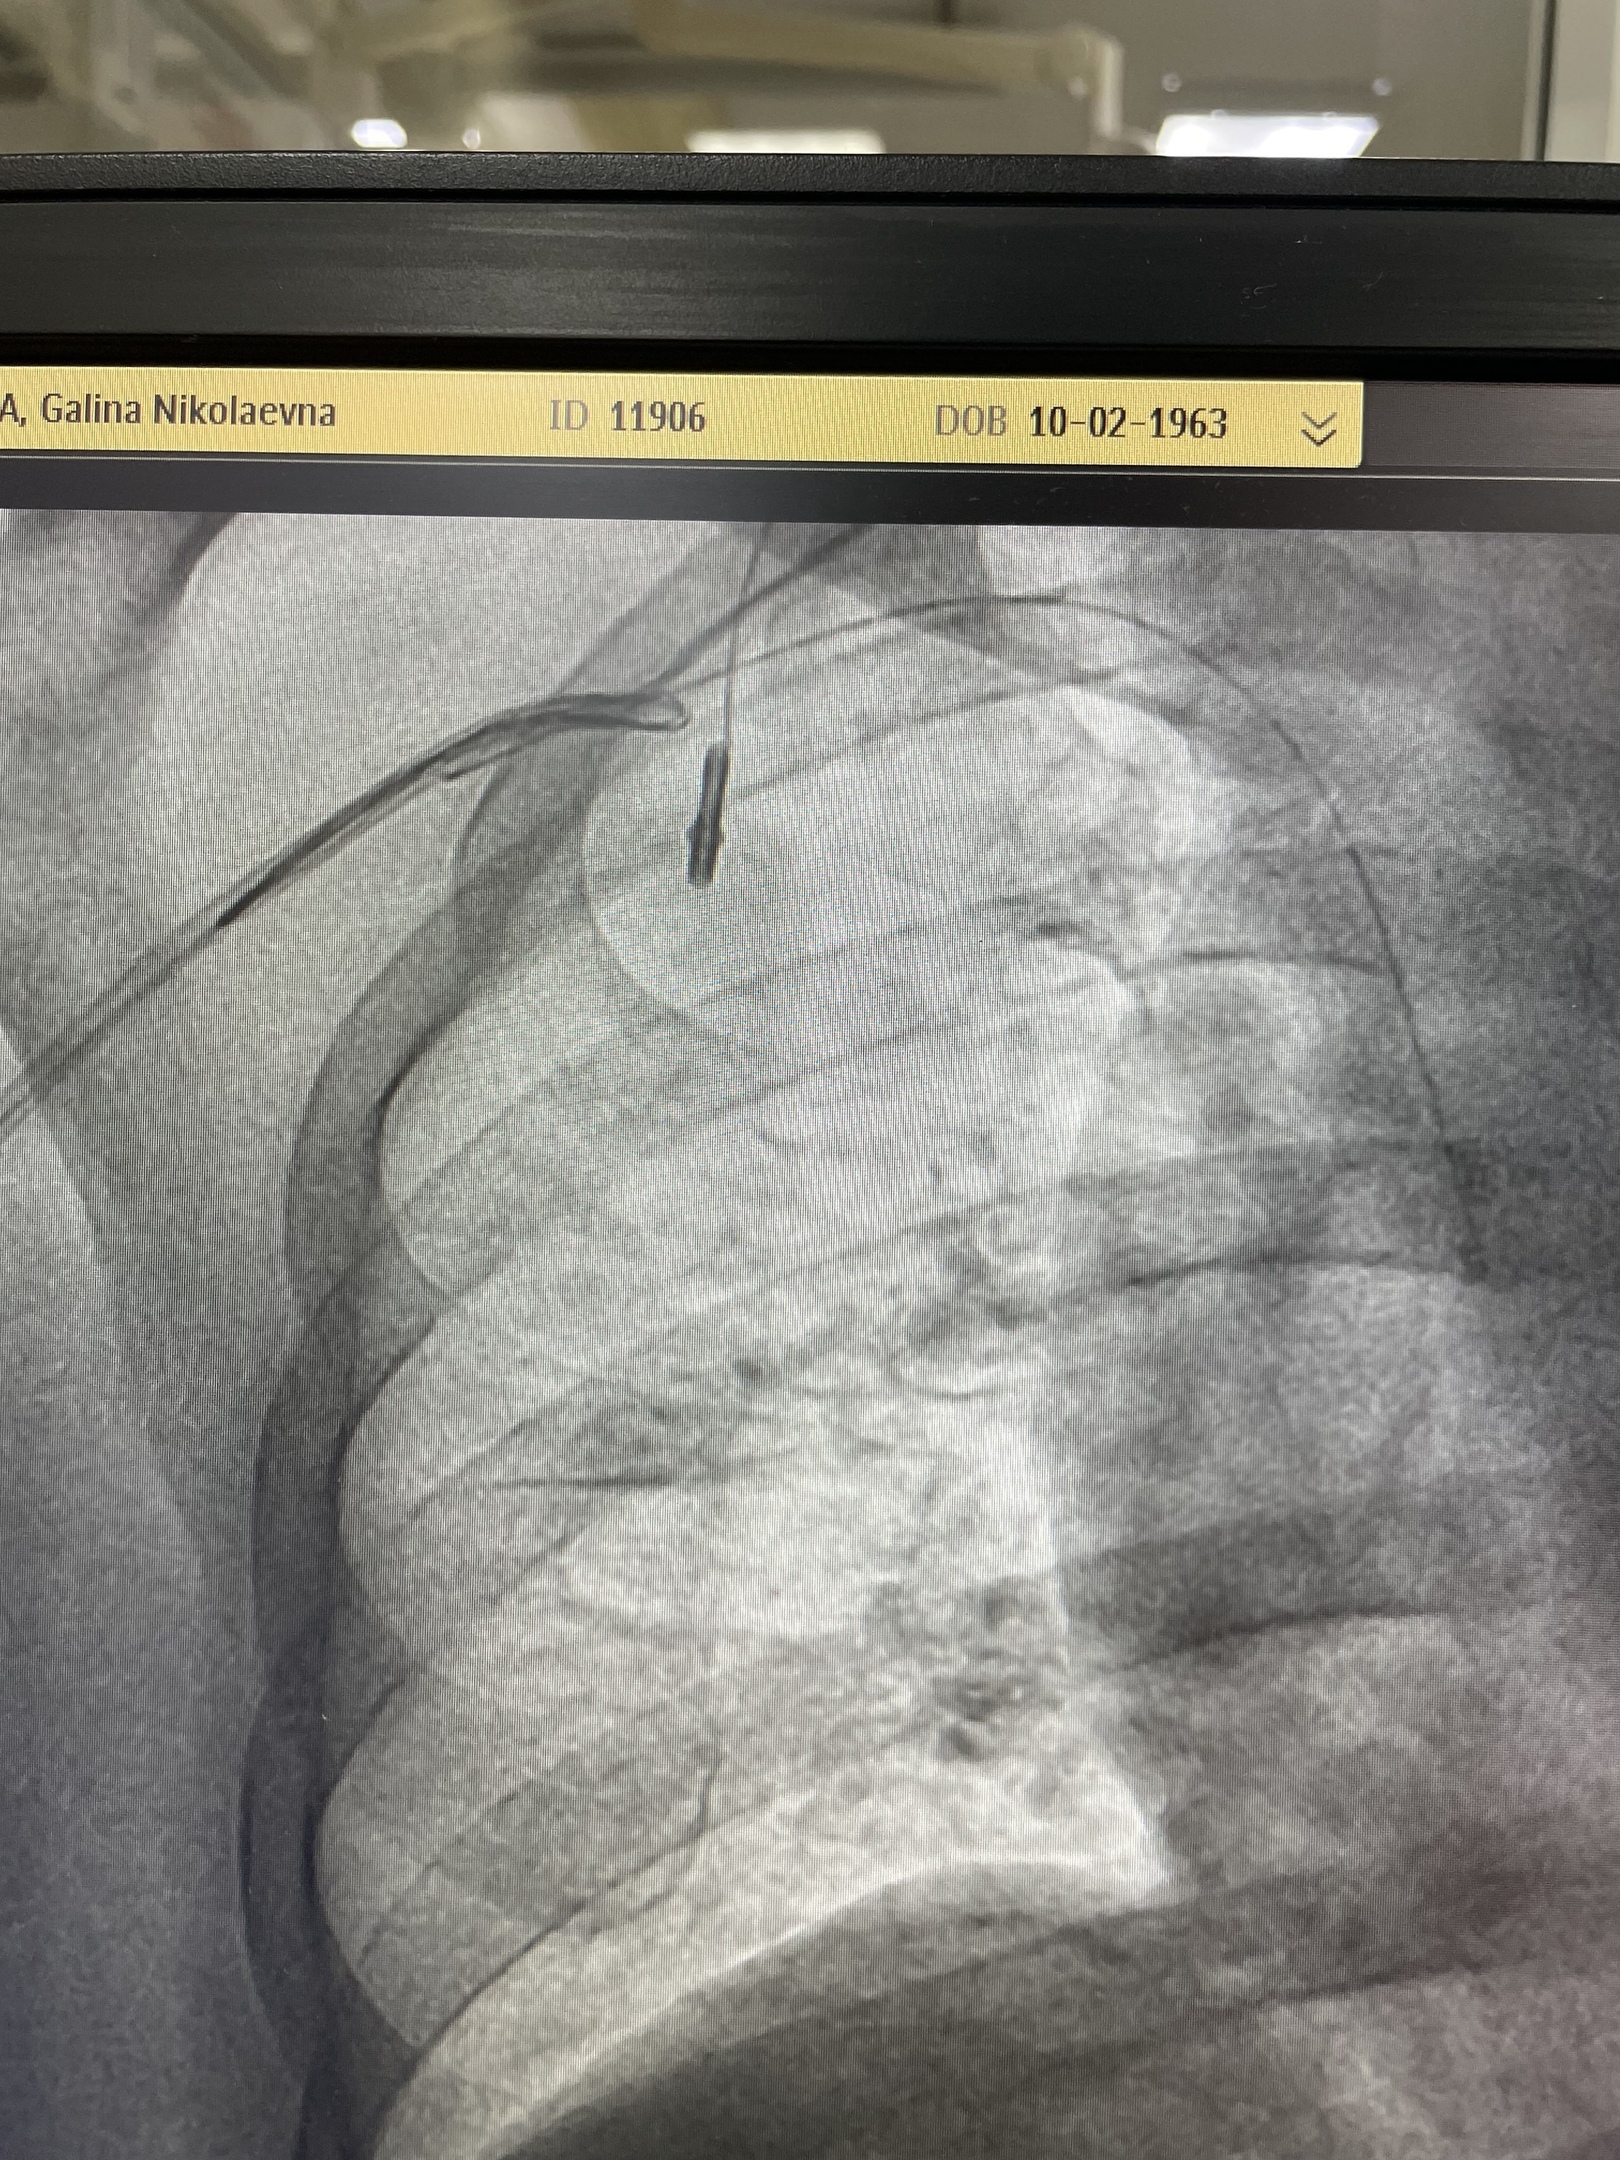

Известно, что пациентка — жительница Ливен. Ещё в 2016-м году женщине установили порт для химиотерапии (устройство для введения препаратов внутривенно). Лечение прошло успешно и завершилось в 2022-м.

Однако порт остался в организме. Проблема выявилась при плановом обследовании. При этом оказалось, что часть системы находится в правом желудочке сердца.

«Дистальный конец системы «врос» в эндотелий правого желудочка, но опыт и мастерство врачей позволили аккуратно отсоединить его», – пояснили в Департаменте здравоохранения Орловской области. Также были удалены другие части инородного тела.